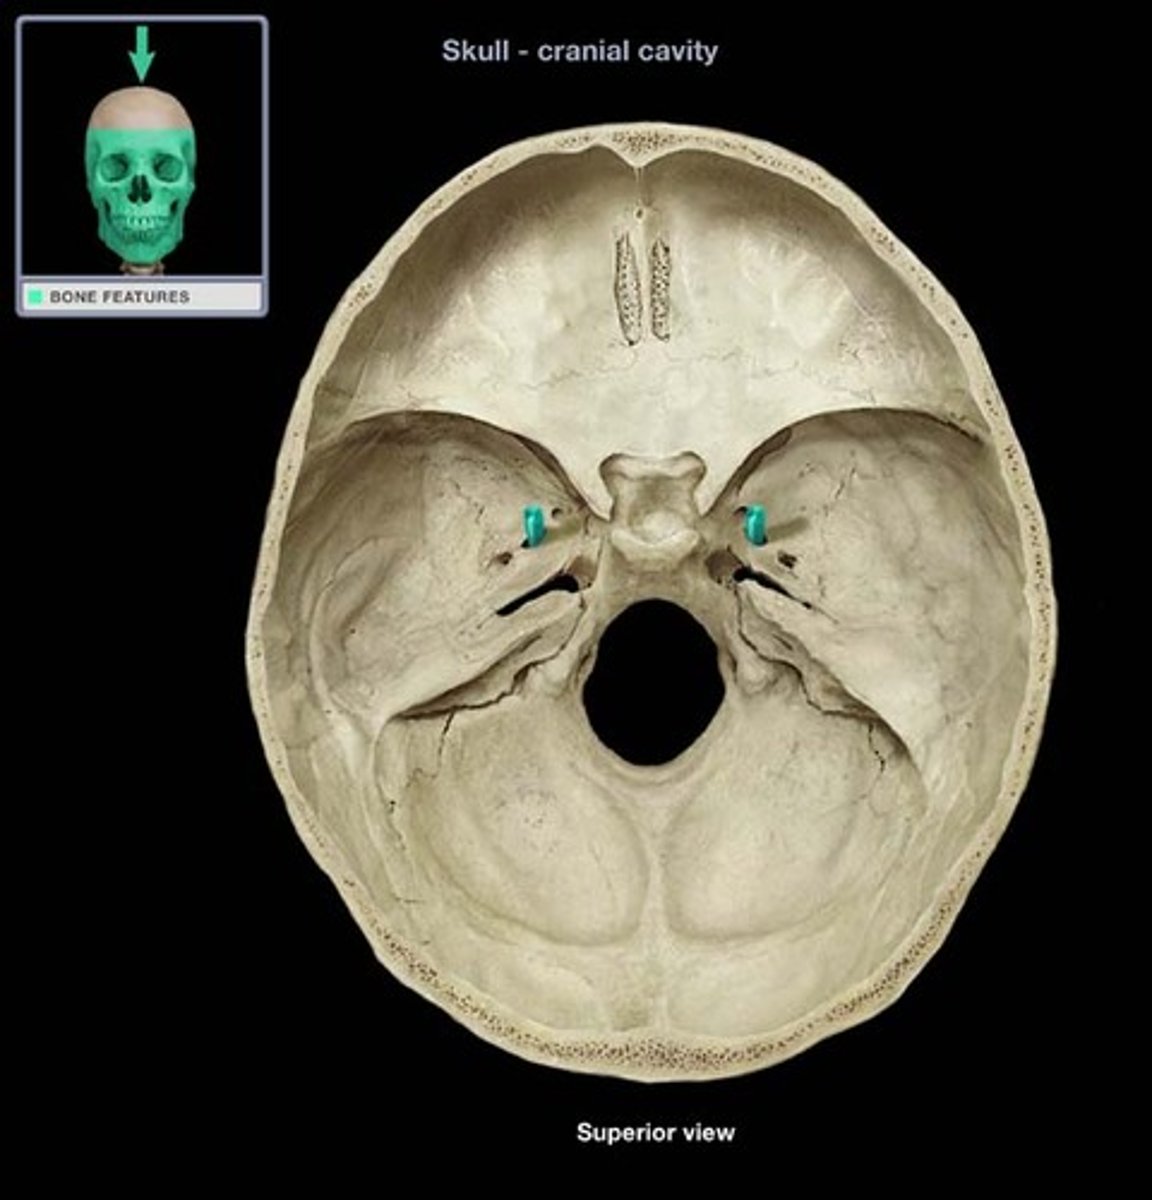

CNI

olfactory nerve: smell, sensory, arise in the olfactory epithelium of the nasal cavity and course dorsally to the olfactory bulb. Associated with the cerebrum. Exit at the foramina in cribriform plate of ethmoid bone.